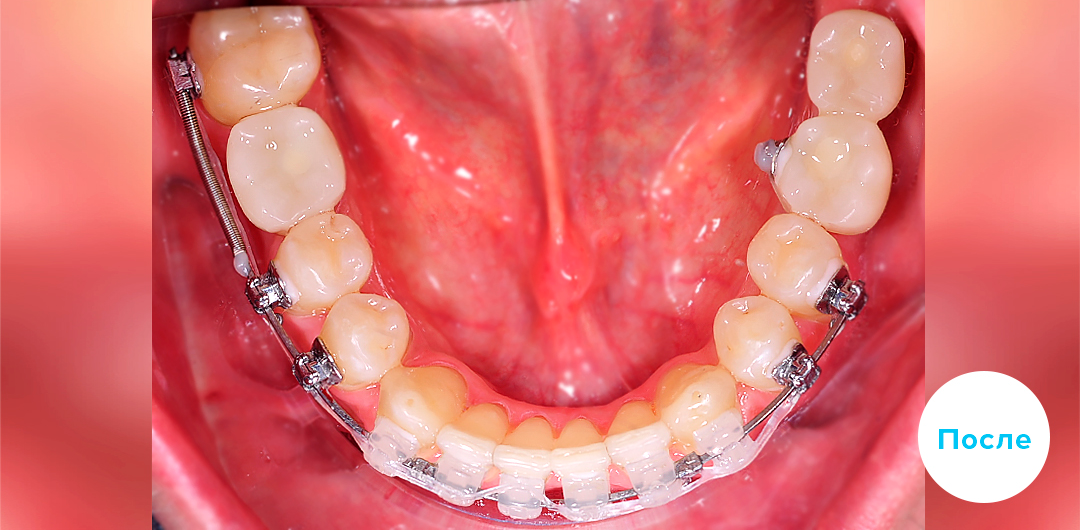

До

После

ИМПЛАНТАЦИЯ 3 ЗУБОВ С ПРЕДВАРИТЕЛЬНОЙ ОРТОДОНТИЧЕСКОЙ ПОДГОТОВКОЙ

Смотреть кейс